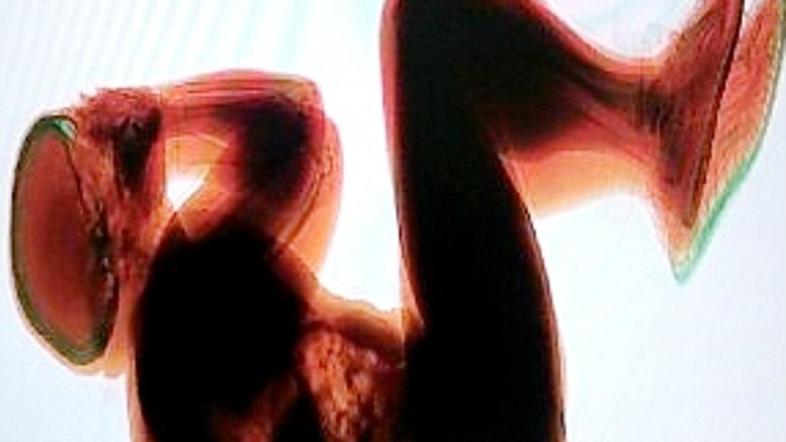

rentgen Žurnal24 main

Zdravniki so v telesu ostarele ženske našli otroški poapnenjen zarodek, star pol stoletja.

Žensko iz Čila, staro okoli 90 let, so svojci odpeljali v bolnišnico, potem ko je padla. Pri ogledu rentgenske slike pa so zdravniki opazili nekaj nenavadnega, v njenem telesu se je namreč nahajal dva kilograma težak zarodek.

Po predvidevanjih zdravnikov je odmrl že v času nosečnosti, vendar ženska ni splavila, zarodek pa je obstal izven maternice in poapnel.

Gre za izredno redek fenomen. Zaradi velikosti je zarodek zavzel velik del ženskine trebušne votline, a je z njim normalno živela pol stoletja. Zaradi njene starosti jo ne bodo operirali, poroča The Independent.